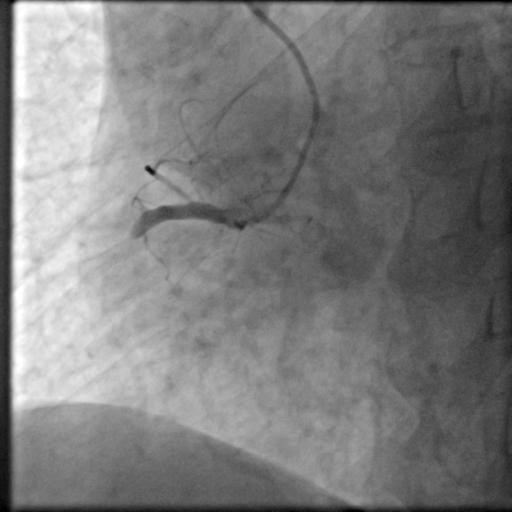

17时30分,陈奶奶已躺在导管室的手术台上,副主任医师朱劲草与王东一起为她进行血管造影。高清的影像图令所有人都禁不住倒吸一口冷气——右冠脉近中段起全部闭塞,仅可见75px左右血管,左冠前降支回旋支也有多处重度病变!

“赶紧开通右冠放支架。”在朱劲草冷静果断的判断下,心内团队成员各就各位,迅速开始了相应处理。